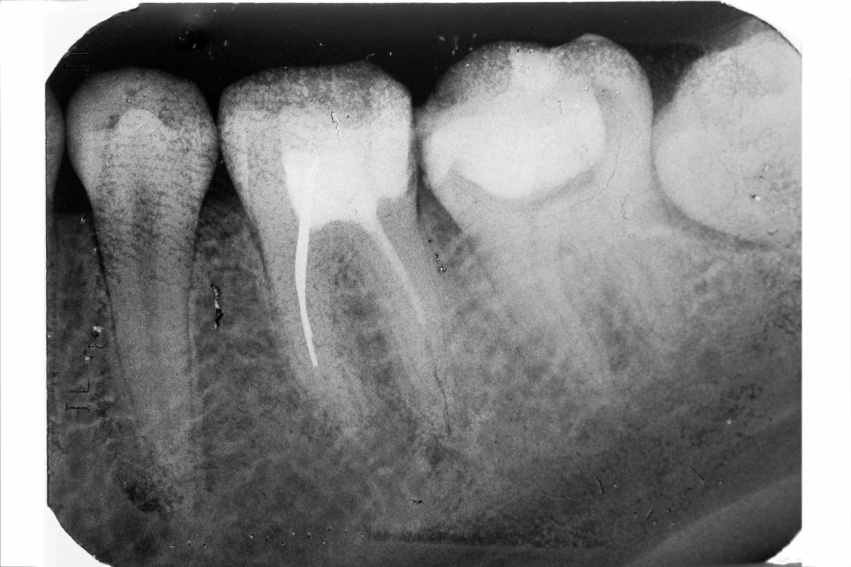

Рис. 2 в Рентгенологический снимок после лечения.

На контрольной рентгенограмме в дистальные каналы введены анкерные штифты, так как большая утрата тканей зуба отражается на его механической прочности.